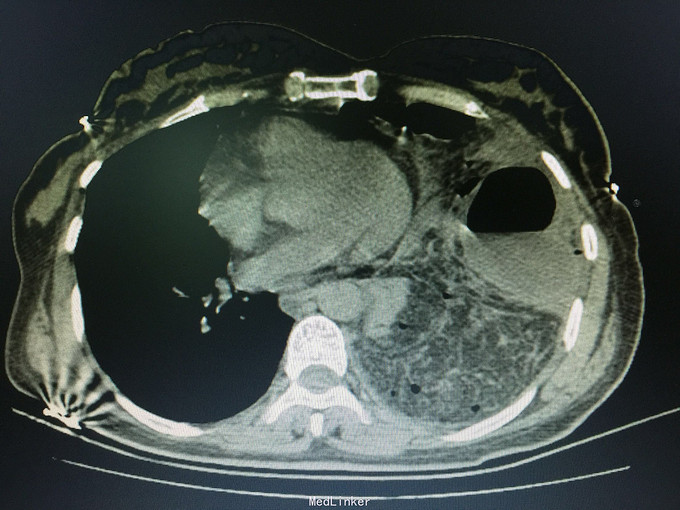

女,41岁, 主诉:腹部胀痛伴不排便、不排气1周, 现病史:一周前无诱因开始腹部胀痛,逐渐加重,以左上腹明显,不排便,不排气,恶心,呕吐数次胃内容物,在当地医院抗炎治疗不见好转,今排腹部平片诊断为“肠梗阻”,来诊。

一般状态可,腹部平坦,未见肠型及蠕动波,脐周压痛,左上腹明显,无腹肌紧张,未及包块,移动性浊音阳性,肠音2次/分。 辅助检查:全腹CT:腹部肠管明显扩张,积液,左侧膈肌局部缺损,腹腔内肠管及系膜组织疝入胸腔。

诊断:膈肌疝,疝内容嵌顿,肠梗阻 处理:手术治疗。